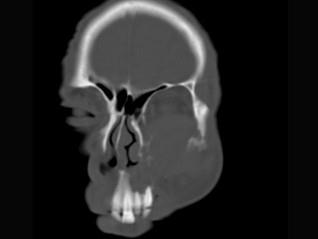

男,65岁,左眼球突出近一年,鼻涕带血,面颊部隆起,同时面颊部有麻木感,CT检查如图,最可能诊断为 ( )